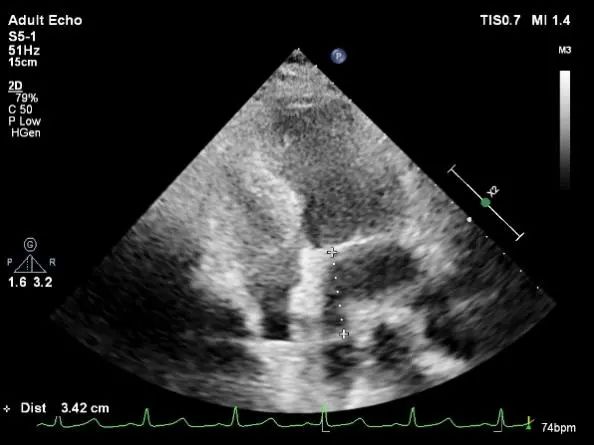

Bicaval 寻找穿刺点

穿刺点距离二尖瓣环3.42cm

穿刺点距离二尖瓣环4.6cm